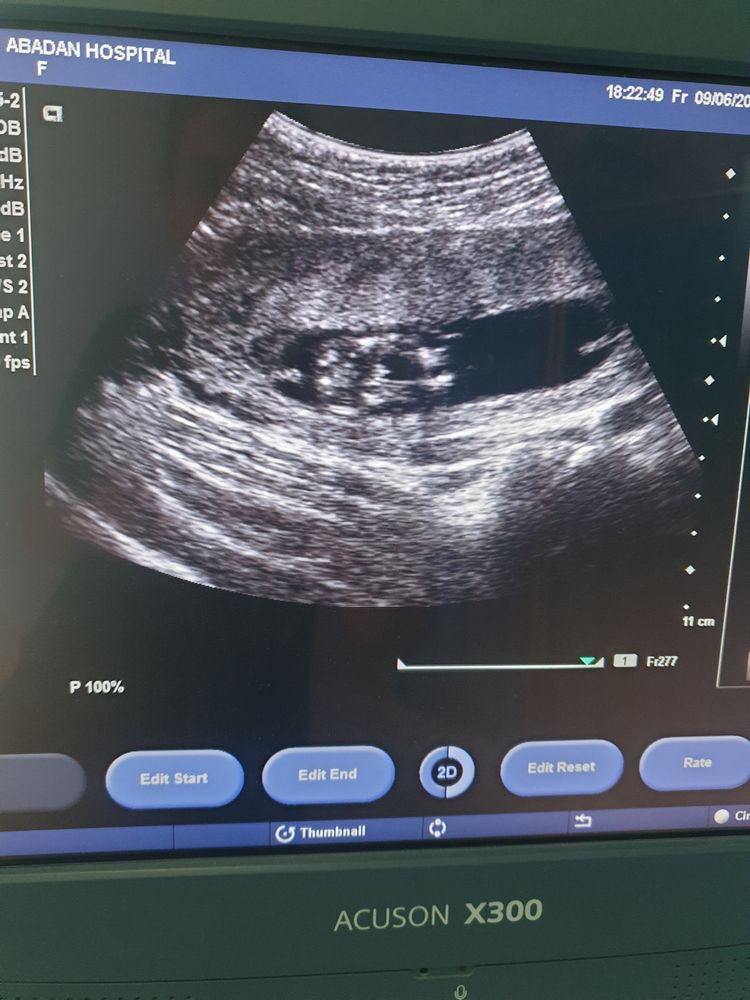

Узи на 15 акушерской неделе

Тоже делала УЗИ в 15 недель ровно, похожая картинка) и тоже сказали - 80% мальчик Изображение

Врач на узи сказала что не 100% мальчик сказала проверить на 2 скрининге там точно скажут